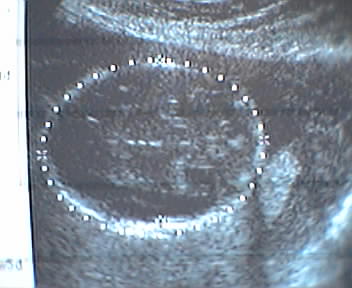

Our third ultrasound today captured our Wascaly Wabbit at 21 weeks. The black and white screen snaps here are of biometric overlays measuring the cranium, femur and heartbeat. Lord, the dotted line around our baby princess girl's head even looks like a crown.

- mike lee - baltimore